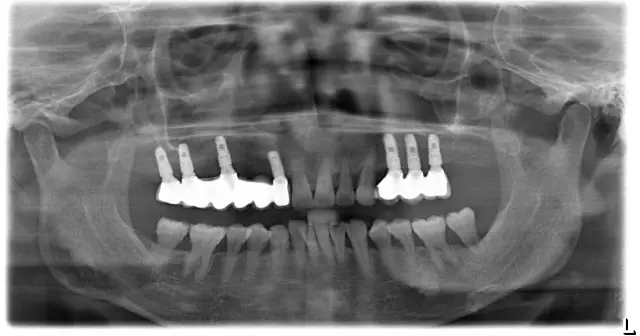

比苏阿姨还年轻的一位美奥种植牙患者,缺牙严重,影响吃饭咀嚼,间接影响了消化和肠胃。

▲种植前

▲种植后

种牙之后让她有了很大的改变,听说是刚刚在山塘街拍完写真照赶过来的,点击语音,直接感受阿姨的分享。